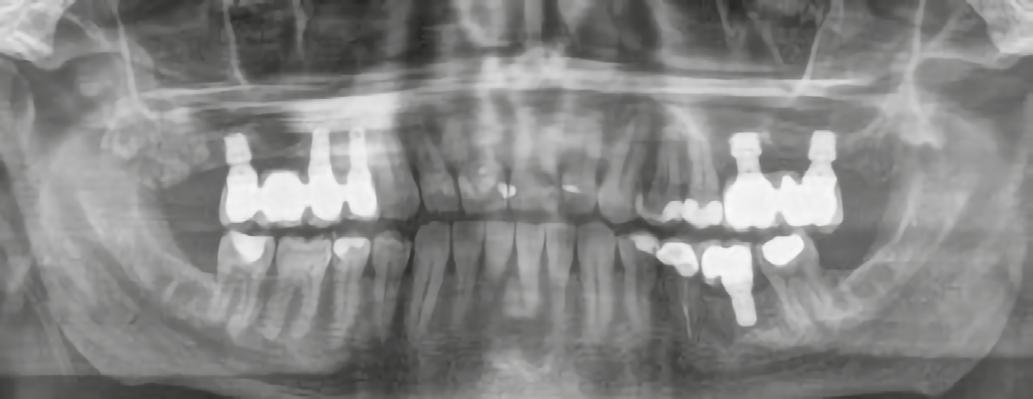

A korai harmicas éveiben járó hölgy rendelőnkbe érkezésének oka a jobb felső nagymetsző fog bizonytalan érzkenysége, elmondása alapján gyermekkorában trauma érte a felső frontrégiót. A frakturált klinikai koronákat kompozittöméssel helyreállították, egyéb kezelést akkor nem tartottak szükségesnek. Az utóbbi hónapokban tapasztalt érzékenység miatt kereste fel rendelőnket. A klinikai vizsgálat (1. és 2. kép) és a CBCT felvétel (3. kép) alapján diagnosztizált külső gyökérreszorpció megoldására a fog eltávolítását, implantátum

bukkális 1. kép: Kiindulási állapot, 2020. január. 3. kép: Kiindulási CBCT felvétel. 2. kép: Kiindulási állapot a palatinális oldal felől.

1. ábra: Megfelelő szájhigiénia – panorámaröntgen. 2. ábra: A 2.5, 2.6 és 2.7-nek megfelelő terület a röntgenfelvételen.

és jelentős mobilitással rendelkezett. A radiológiai vizsgálat után egyértelműen látszódott, hogy a fogon még nem végeztek gyökérkezelést. A 2.6-os és 2.7-es fogaknak megfelelő területen az arcüreg kiterjedése jelentős volt, vertikális csontmennyiség szignifikánsan csökkent (1. és 2. ábra).